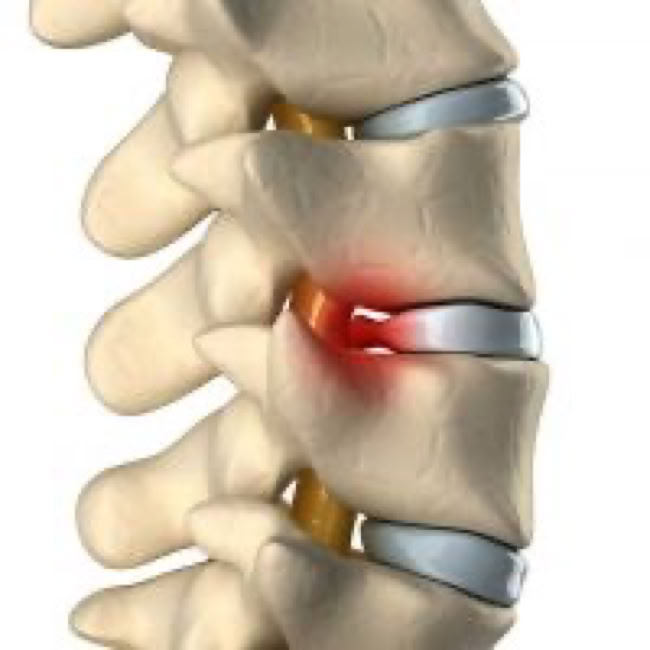

The annulus can tear or rupture anywhere around the disc. If it tears and no disc material is ruptured, this is called an annular tear and can be extremely painful as the outer fibers carry pain signals. This tear will heal with scar tissue over time but is more prone to future tears and injury. If the annulus tears and the center nucleus can squeeze out, a piece of the disc from the center or outside portion can break off and extend outward. A disc herniation, by definition, is displacement of disc material beyond the normal confines of the disc space. The terms disc protrusion, disc bulge, disc herniation, ruptured disc, and slipped disc all mean the same thing and imply that disc material has left the normal disc space.

If disc material herniates, or squeezes out, this can put pressure on the spinal cord or spinal nerves. This can cause severe pain in the path of the nerve being pinched. Pressure against the nerve root from a herniated disc can cause numbness and weakness along the nerve. When the nerve root is inflamed, the added pressure may also cause vague, deep pain and/or cause sharp, shooting pain to radiate along the pathway of the nerve. There is also evidence that the nucleus pulposus material is quite acidic and causes a chemical irritation of the nerve roots. The consistency of a disc depends upon whether it is the outer tough annular portion or the central soft nuclear portion. In lay terms many compare the consistency of a disc herniation to that of lobster or crab meat.